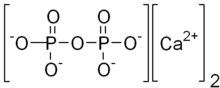

| Calcium pyrophosphate dihydrate disease | |

Calcium pyrophosphate dihydrate (CPPD) crystal deposition disease, also known as pseudogout and pyrophosphate arthropathy, is a rheumatologic disease which is thought to be secondary to abnormal accumulation of calcium pyrophosphate dihydrate crystals within joint soft tissues.[1] The knee joint is most commonly affected.[2] The disease is metabolic in origin and its treatment remains symptomatic.[3]